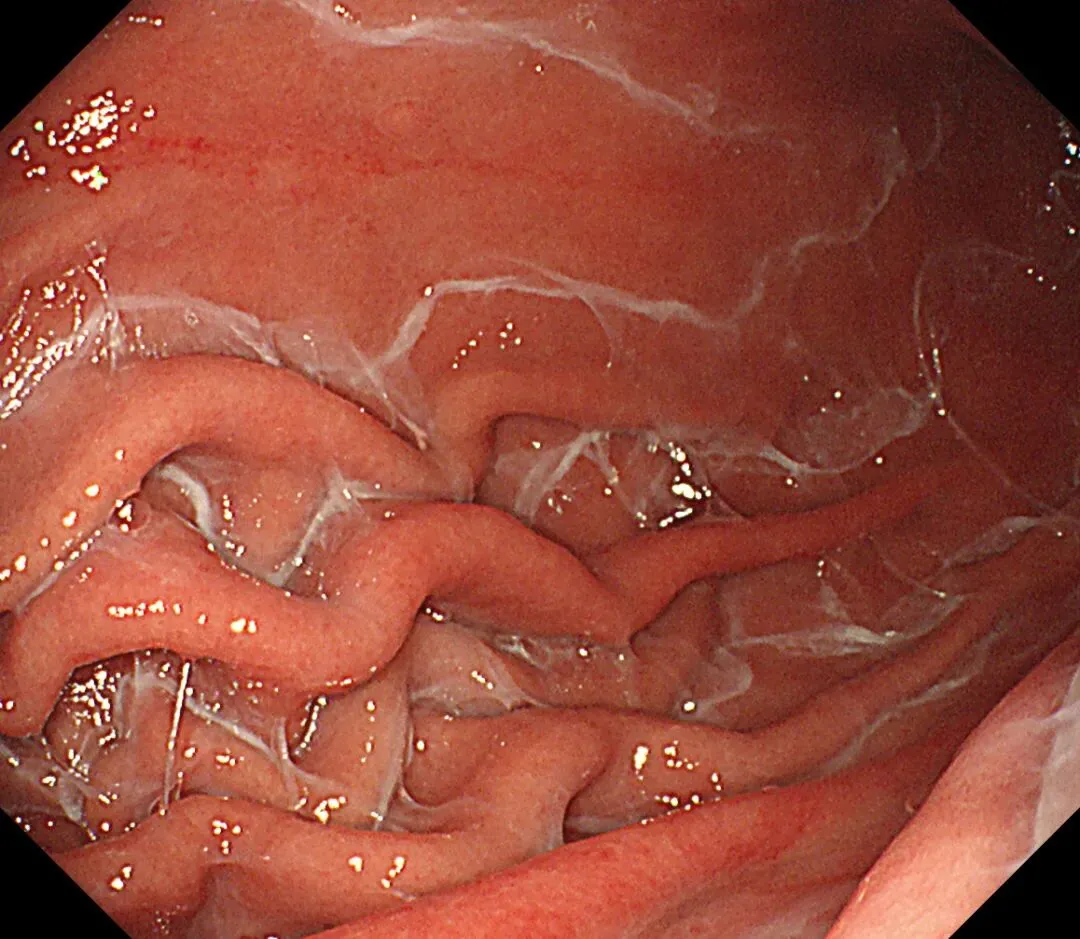

顽固性黏液(sticky adherent dense mucus):多呈灰黄色、黄白-乳白色,黏稠度高,附着于胃壁不易剥离,强行去除容易出血,也常有人称之为酒糟样固形物,多见于自身免疫性胃炎(AIG)进展期患者。

顽固性黏液case1,确诊为A型胃炎患者👇

文献报道此类型黏液因水洗不易去除,为产尿素酶弱阳性细菌的立足之处,为“泥沼除菌”的原因。

夹带小小科普:泥沼除菌(endless eradication) 通常指在自身免疫性胃炎(AIG)患者中,由于胃酸分泌显著降低,无论有无合并幽门螺杆菌感染,除菌治疗后胃酸仍无法恢复正常,幽门螺杆菌以外的产尿素酶杂菌(来源于口腔或肠道)仍可以在胃内栖息,检查13碳呼气试验持续阳性(文献报道非Hp感染的AIG患者13C-UBT平均值为5.4),导致反复除菌治疗后仍然“失败”。so,临床上遇到反复除菌失败的患者,需考虑到AIG的可能性

个人体会:蛛网状黏液与P-CAB药物相关,顽固性黏液与AIG相关,两种胃内环境都一样是胃酸缺乏,据说胃内PH升高可导致蛋白质变性形成“乳状”黏附,也据说是因为胃酸缺乏导致化生的黏液分泌细胞大量增多,分泌异常成分的高粘稠度黏液,两者的形成机制和内镜表现是比较类似的,不同之处在于蛛网状黏液除了比较“网状”之外,还比较“拉丝”、“乳白”,顽固性黏液比较“果冻”、“淡白”、"广泛涂层"、“紧贴大地”。。。词穷了,从小没学过语文课,还需多看书、观察更多病例加以总结,请各位老师们指正。。。